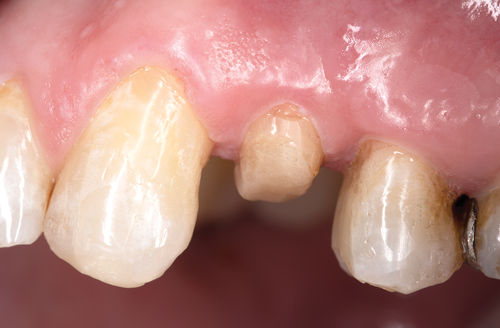

Restorative failure of an existing amalgam restoration on the maxillary left first premolar from recurrent caries is documented here (Figure 2). The periapical radiograph revealed an extensive carious lesion extending into the pulp chamber. After clinical and radiographic evaluation, a treatment plan was discussed with the patient that included endodontic therapy, crown lengthening, and reinforcing the root and supporting the tooth-restorative complex with a fiber-reinforced post and core system.

Fig 3. After endodontic treatment, crown lengthening was performed to develop an ideal ferrule effect.

Figure 3

Fig 4. An adequate collar effect of 2 mm of sound tooth structure would provide an anti-rotational feature for the stability of the crown.

Figure 4

Fig 5. Buccal view of optimal ferrule effect with a healthy biological framework.

Figure 5